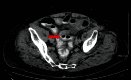

Jejunal pseudo-diverticulosis is a rare acquired herniation of the mucosa and submucosa through weakened areas of the muscularis mucosa of the mesenteric aspect of the bowel. They are asymptomatic in the majority of cases; however, they can present with a wide spectrum of non-specific symptoms such as chronic abdominal discomfort, postprandial flatulence, diarrhoea, malabsorption and steattorhoea. In up to 15% of cases, more serious acute complications may arise such as the development of intestinal obstruction, haemorrhage or as in our case, localized peritonitis secondary to perforation. Perforation carries an overall mortality rate of up to 40% and exploratory laparotomy followed by copious lavage with segmental resection and primary anastomosis remains the mainstay of managing such sequalae of jejunal pseudo-diverticulosis. Our case report highlights the importance of maintaining a high clinical suspicion of a perforated jejunal diverticulum in an elderly patient presenting with an acute abdomen.